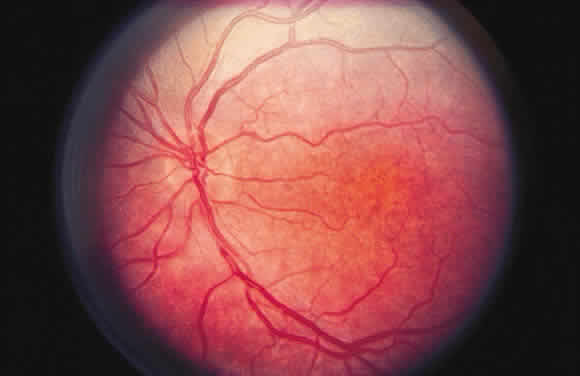

ischemia of the retina, as reflected clinically by a central retinal

artery occlusion (Fig. 35), is seen ophthalmoscopically as a gray-white opacification of the retina

and likely reflects this metabolic disturbance.  Fig. 35. Acute central retinal artery occlusion demonstrating generalized opacification

of the retina in the posterior pole except for the “cherry-red

spot” fovea and a small area of “normal” retina

adjacent to the disc supplied by a small cilioretinal artery. Fig. 35. Acute central retinal artery occlusion demonstrating generalized opacification

of the retina in the posterior pole except for the “cherry-red

spot” fovea and a small area of “normal” retina

adjacent to the disc supplied by a small cilioretinal artery.